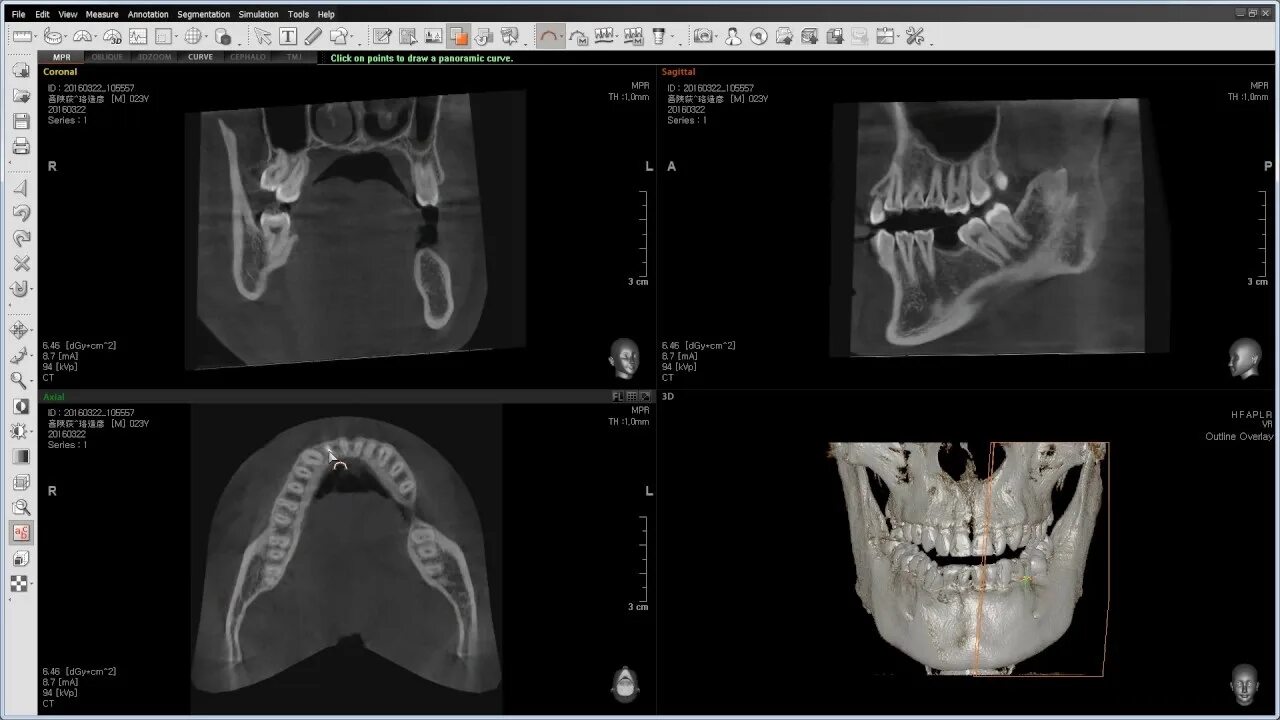

Picasso кт